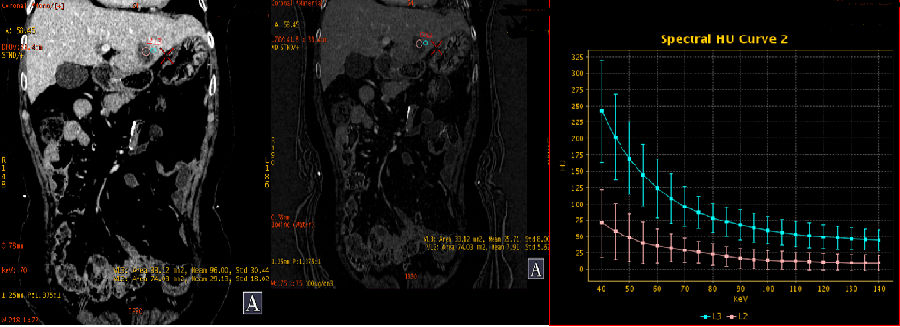

2、门脉期能谱曲线分析

肝右叶两个病灶能谱曲线接近一致(绿/深蓝);病灶边缘及内部进一步强化,CT值升高,碘基图碘含量增加

3、延迟期能谱分析

左侧病灶CT值及碘含量持续升高

肝右叶两个病灶能谱曲线仍然接近一致